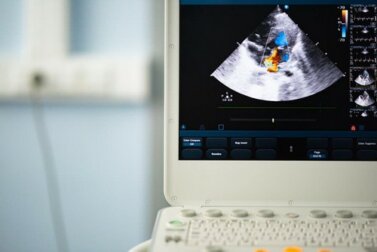

Durante l’analisi si farà uso dello stetoscopio per cercare di individuare le palpitazioni irregolari del cuore ed eventuali segnali di soffio cardiaco. Per escludere un caso di valvola aortica bicuspide, verrà eseguito un ecocardiogramma in grado di valutare il funzionamento del cuore.